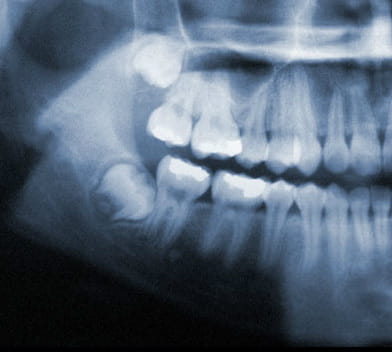

X-Ray of wisdom teeth

Wisdom teeth generally begin to form in your pre-teen years. By late teen years, the crown of the wisdom teeth will begin to erupt through the gums if there is adequate room. By mid twenties, your wisdom teeth will either be able to fully erupt or will have become impacted. Early removal of wisdom teeth makes the procedure easier for the patient to tolerate and promotes faster healing after wards. By your early forties, the wisdom teeth roots have become fully anchored to the jawbone and if required to be extracted, will be much harder and will need more time to heal.

Wisdom teeth under ideal circumstances should grow in straight like any other tooth. However, it is common for wisdom teeth to become impacted inside the jaw or just under the gums. If this occurs, your wisdom teeth should be removed.

Wisdom teeth also known as third molars are the last teeth to erupt into the mouth. Wisdom teeth typically appear around a person's mid-twenties but can erupt much later. If wisdom teeth don't have enough space symptoms can occur. The wisdom teeth may only partially erupt or might not come through at all. Dentists designate wisdom teeth 'impacted' if they are wholly or partly blocked from eruption into the mouth. The tooth may lie at an angle and remain tipped against an adjacent tooth. Impacted wisdom teeth can cause problems like pain and swelling; The mouth could ache when stretched open wide or it may be difficult to open your mouth. Tenderness when chewing and biting may occur. Earaches may develop from the spread of pain in the mouth. Symptoms may be intermittent but can begin anytime without warning. If you are experiencing symptoms, it is best to get treatment 'usually removal' as soon as you can to avoid potentially expensive and painful complications.